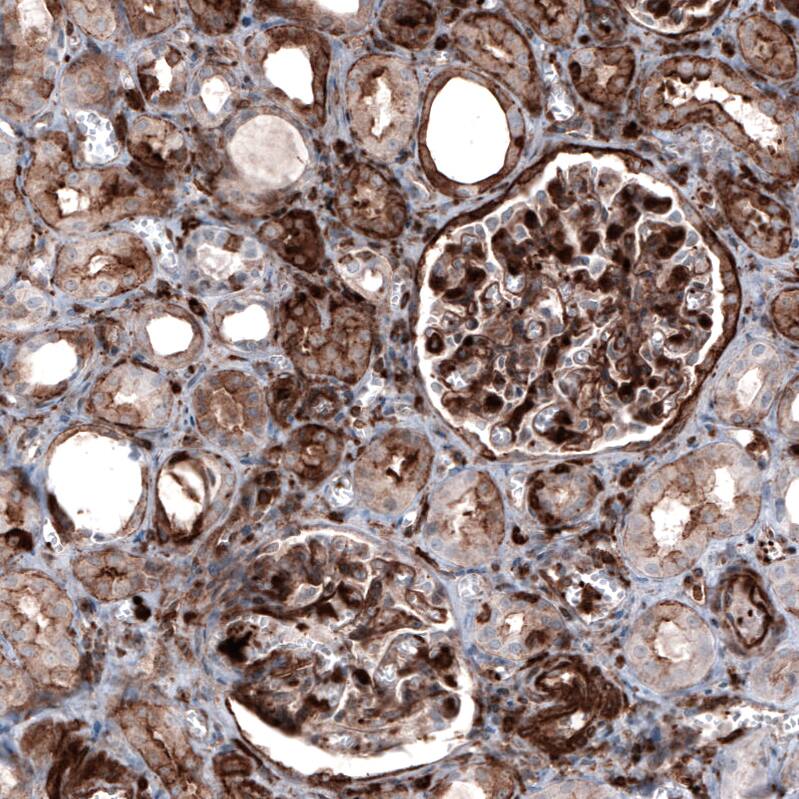

Staining of human kidney shows moderate to strong cytoplasmic and membranous positivity in cells in glomeruli and in tubules.